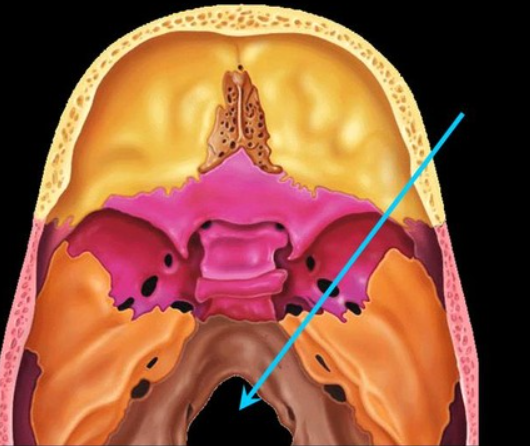

foramen magnum

the big circular hole in the middle of the skull